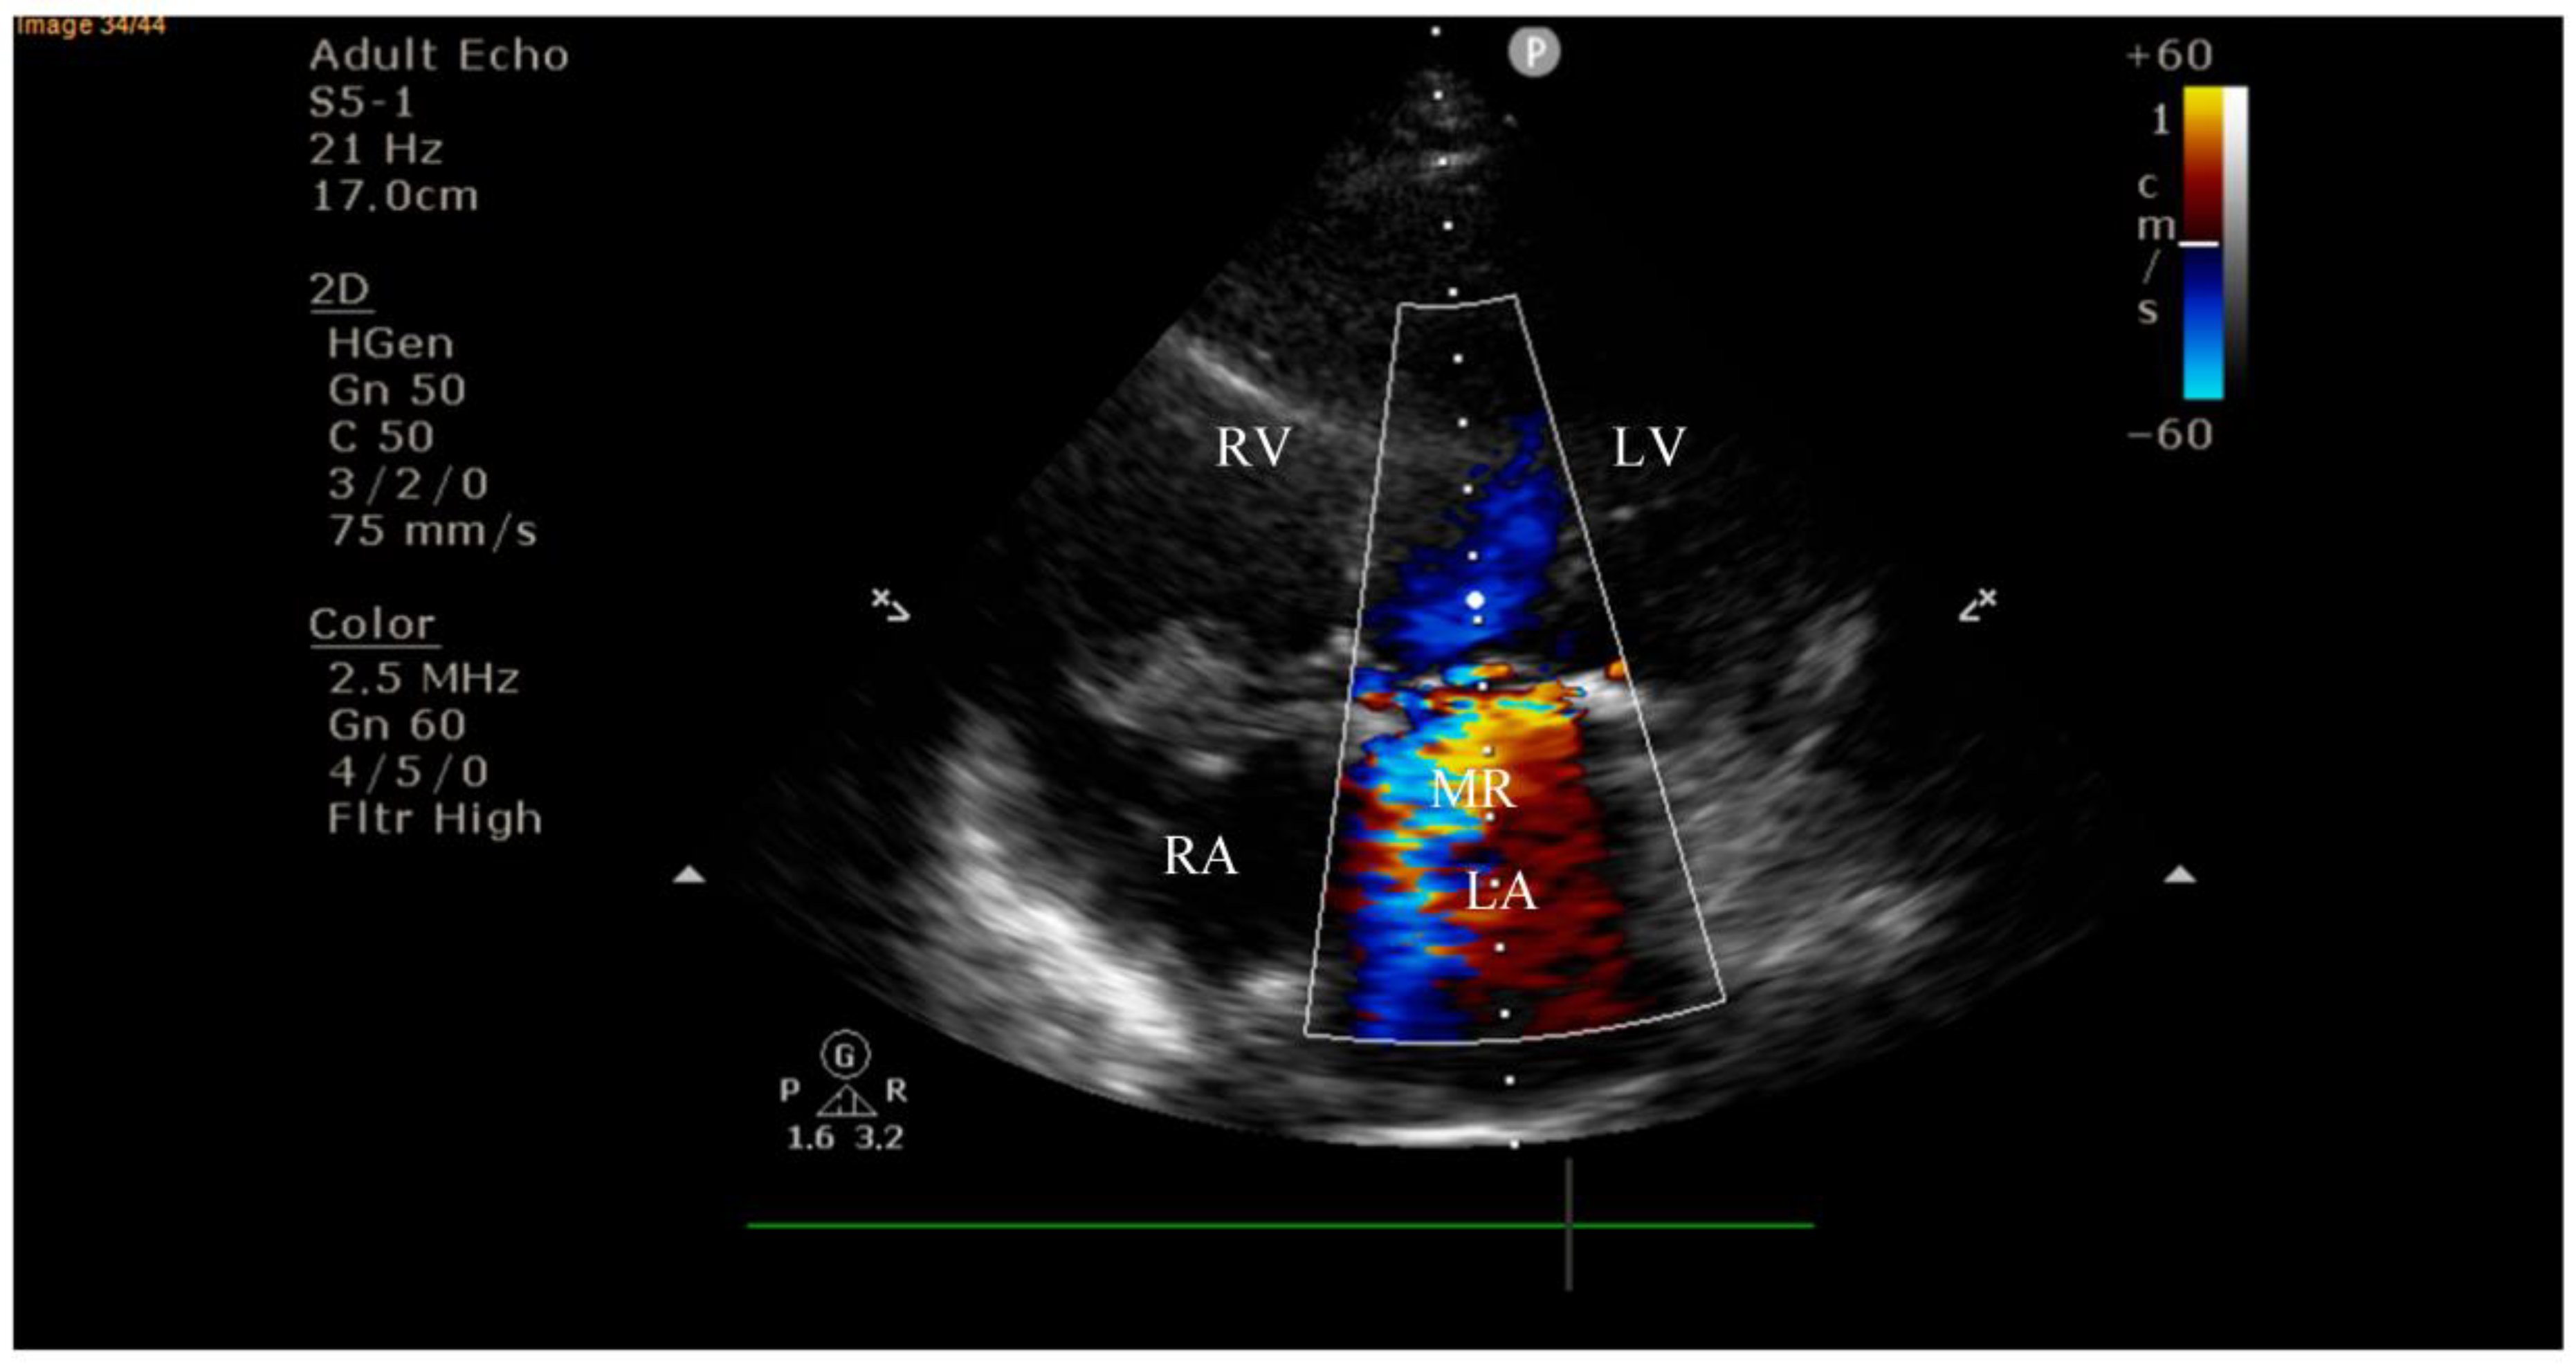

4.2. Diagnostic Findings: Mitral Valve Dysfunction and Embolic Phenomena